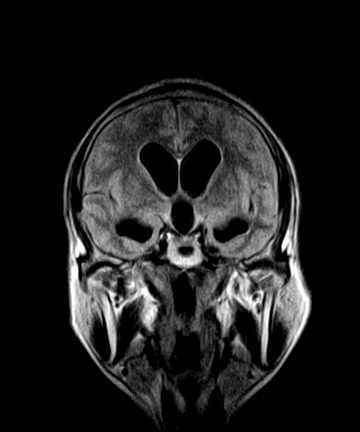

标题: MRI2064:少见病例。男性52,视力下降多年。 [打印本页]

标题: MRI2064:少见病例。男性52,视力下降多年。

四脑室区见混杂信号占位影,脑室系统扩张明显,临近结构显著受压称位,患者52岁,多考虑室管膜瘤可能性大

考虑第四脑室室管膜瘤并阻塞性脑积水。

考虑第四脑室室管膜瘤并梗阻性脑积水;部分性空蝶鞍;左侧上颌窦粘膜下囊肿。

考虑第四脑室室管膜瘤【血供丰富血管母细胞瘤可能】并梗阻性脑积水;部分性空蝶鞍;左侧上颌窦粘膜下囊肿。

比较典型的脉络丛乳头状瘤并脑积水,鉴别小脑蚓部血管母细胞瘤。